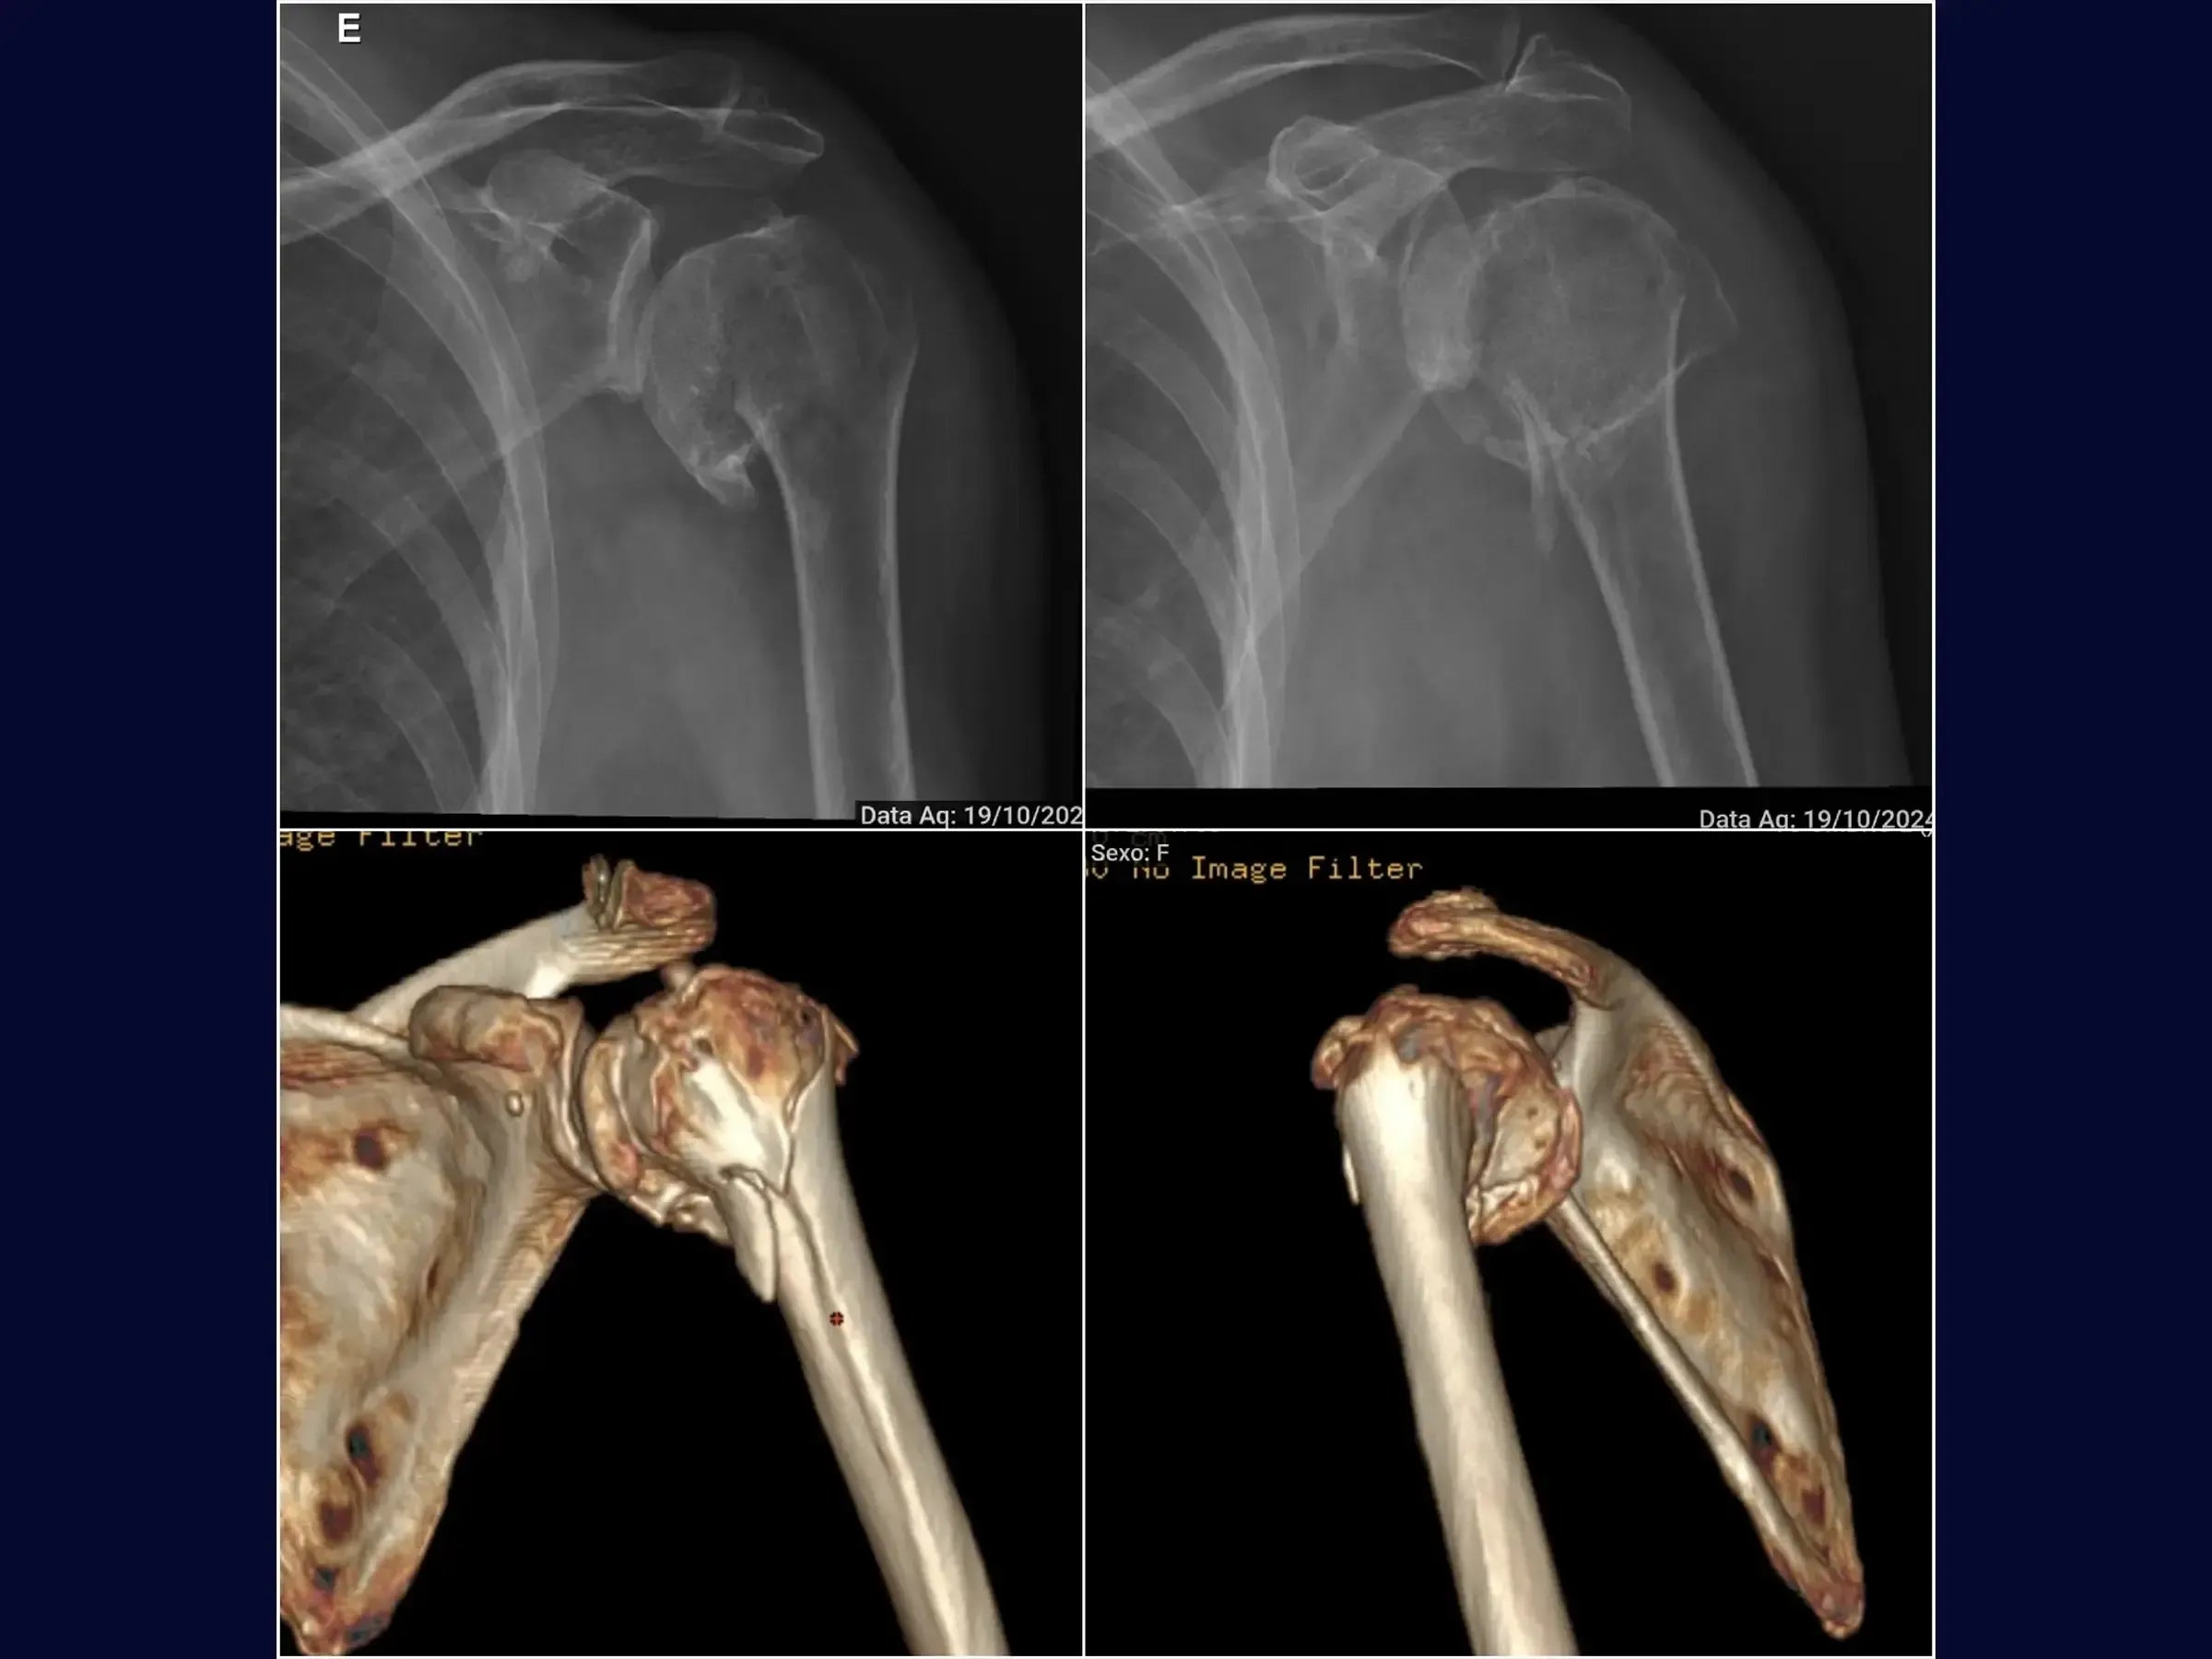

Domine o tratamento de fraturas do úmero proximal. Este treinamento oferece uma imersão técnica na osteossíntese com placa via acesso deltopeitoral, apresentada em vídeo 4K sob a perspectiva do cirurgião, abordando o manejo em pacientes idosos com artrose glenoumeral assintomática.

- Osteossíntese de fraturas do úmero proximal com placa.

- Redução da Fratura Guiada: Abordagem sistemática para redução da fratura utilizando manipulação do braço e laçadas, com pontos de referência anatômicos como o sulco do bíceps e vértices da fratura para controle de alinhamento e rotação.

- Avaliação Intraoperatória Detalhada: Análise radiográfica para verificação da altura da placa, redução da fratura e centralização da placa, assegurando a distribuição adequada dos parafusos.

- PDF Detalhado: Este PDF aborda o tratamento cirúrgico de fratura do úmero proximal em pacientes idosos com artrose glenoumeral assintomática, detalhando o posicionamento, acesso deltopeitoral, manejo do cabo longo do bíceps, tenotomias, exposição de tuberosidades e manguito rotador, redução da fratura, fixação com placa e parafusos, tenodese e enxerto ósseo.